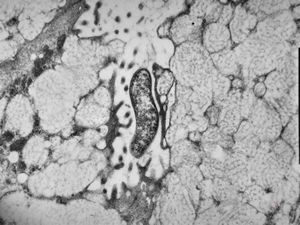

M,67y. | herpetic encephalitis (parafin embedded sample)